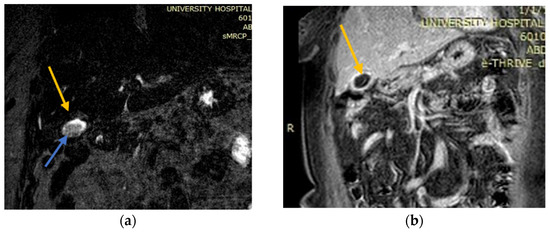

2.2. Case 2